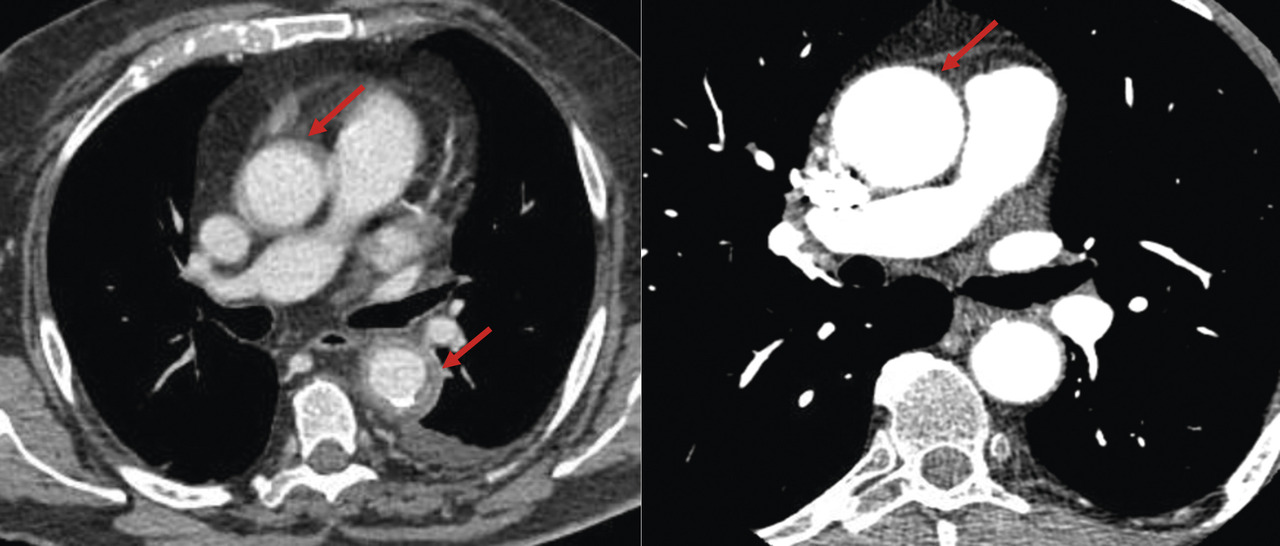

La recherche d’une aortite est recommandée chez tout patient ayant une artérite à cellules géantes. il peut en effet exister des lésions inflammatoires de l’aorte (40 % des cas), parfois associées à une dilatation voire un anévrisme de l’aorte (fig. 2), ce qui imposera une surveillance spécifique. Dans de rares cas, ces anévrismes peuvent être d’emblée compliqués, avec des risques de rupture ou de dissection de l’aorte. La recherche d’une aortite peut se faire par angio-tomodensitométrie [angio-­TDM] (fig. 5), angio-IRM, ou encore par tomographie par émission de positons au 18-F déoxyglucose (TEP) idéalement couplée à une tomodensitométrie (TEP-TDM).

L’artérite à cellules géantes s’accompagne d’un surrisque d’anévrisme de l’aorte, notamment de l’aorte thoracique, et ces lésions morphologiques sont parfois diagnostiquées plusieurs années après le diagnostic initial (fig. 5). Une imagerie de l’aorte (angio-TDM, IRM) à 2-5 ans du diagnostic d’artérite à cellules géantes est donc utile pour dépister ces anévrismes.